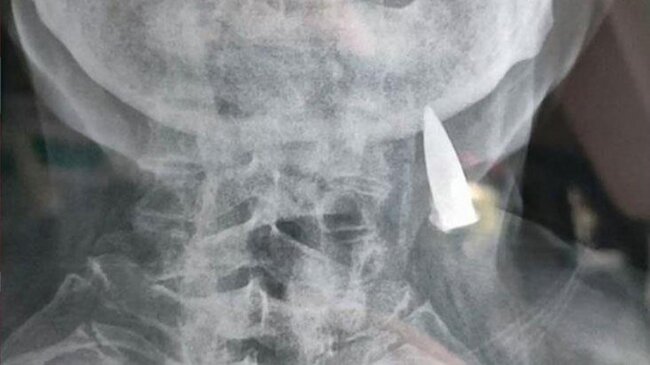

Baş ağrısı şikayəti ilə həkimə gedən 95 yaşlı kişinin rentgen nəticələri həkimləri şoka saldı

AZXEBER.COM xarici mediaya istinadən xəbər verir ki, 95 yaşlı Zhao He baş ağrısı şikayəti ilə getdiyi xəstəxanada rentgen çəkdirib.

Nəticələri alan həkimlər gördükləri detala heyran qalıblar. Kişinin boynunda bir güllə tapan həkimlər bu güllənin 70 ildir kişinin boynunda olduğunu müəyyən ediblər.